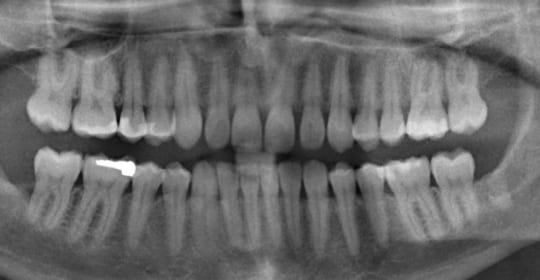

According to the NIH, recommended exposure to ionized radiation is 20mSv (millisieverts) per year, and 400mSV per lifetime. Again, I know cancer patients are like… “but…”. One single dental x-ray produces an exposure of .007mSv. So, if all you have to worry about is annual dental x-rays, you are pretty safe when it comes to exposure.

What prompted this post, was a simple question on one of the forums I am involved with, “should I be exposed to a CT scan given my radiation history?” None of my doctors rush to schedule me for any kind of scan or x-ray because of how much I have been through. But seriously, is a dental or chest x-ray really going to cause any more problems given what I received?